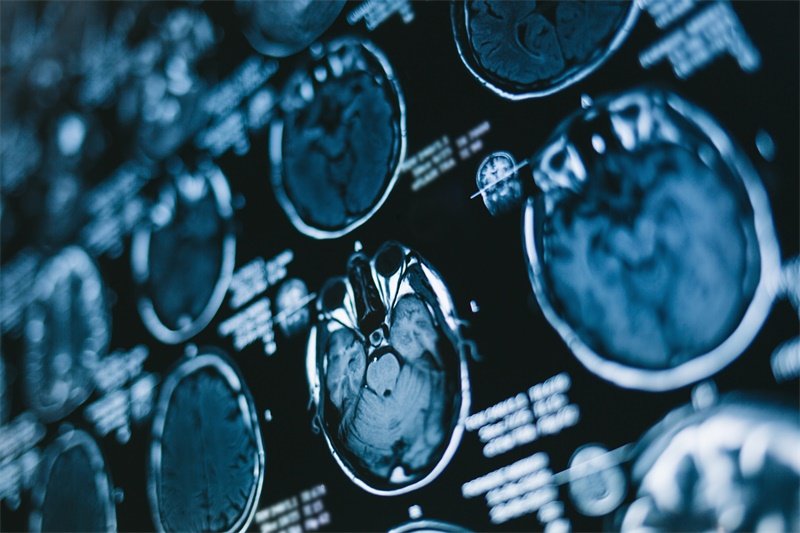

烟雾病是一种罕见的脑血管闭塞病,成人患者常以脑出血发病,再出血风险高、预后差。血管搭桥手术是主要治疗手段,但颞浅动脉大脑中动脉双旁路术到能否有效预防下一次灾难性的出血呢?...

在神经外科领域,烟雾病一直是个棘手难题。患者大脑主要血管逐渐闭塞,代偿形成脆弱异常的烟雾状血管网,不仅容易导致脑缺血,更可能在搭桥手术后出现致命的出血性脑高灌注综合征(...

烟雾病患者接受颞浅动脉-大脑中动脉(STA-MCA)双吻合术,就像为缺血的大脑搭建生命通道,但术后潜藏的出血性脑高灌注综合征(CHS),却可能成为致命隐患。 INC国际神经外科脑血管大咖川岛...